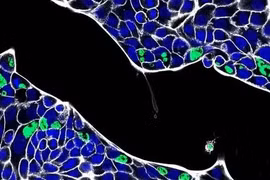

Một nghiên cứu cho thấy khi phá vỡ protein cũ, proteasome liên tục giải phóng các peptide kháng khuẩn, đóng vai trò quan trọng trong tuyến phòng thủ đầu tiên và tiêu diệt các vi khuẩn gây hại.